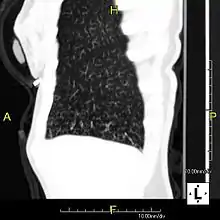

Sagittal reformatted CT image showing "tree in bud" appearance of impacted distal small airways in primary ciliary dyskinesia

In radiology, the tree-in-bud sign is a finding on a CT scan that indicates some degree of airway obstruction.[1] The tree-in-bud sign is a nonspecific imaging finding that implies impaction within bronchioles, the smallest airway passages in the lung. The differential for this finding includes malignant and inflammatory etiologies, either infectious or sterile. This includes fungal infections, mycobacterial infections such as tuberculosis or mycobacterium avium intracellulare, bronchopneumonia, chronic aspiration pneumonia, cystic fibrosis or cellular impaction from bronchovascular spread of malignancy, as can occur with breast cancer, leukemia or lymphoma.[2] It also includes lung manifestations of autoimmune diseases such as Sjögren syndrome or rheumatoid arthritis.[3][4]

Histopathologic studies have shown that the tree-in-bud pattern is caused by demarcation of the normally invisible branching course of the peripheral airways, which usually results from bronchioles being plugged or blocked with mucus, pus or fluid. In addition, dilated and thickened walls of the peripheral airways and peribronchitis can make the affected bronchioles more easily visible, as is seen in patients with cystic fibrosis.